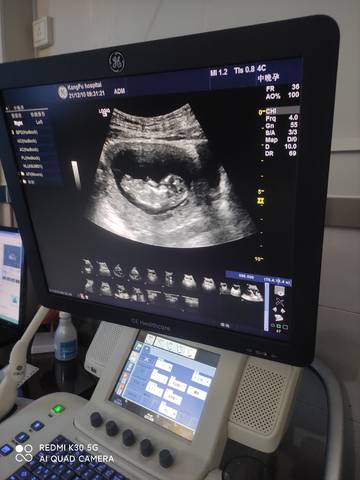

NT秒过,有会看男女的吗

你好。我们是判断不了男宝宝跟女宝宝的,孕期定期检查,我觉得宝宝健康就好的。祝心想事成 。

你好亲爱的,通过这个来判断男孩女孩是不太准确的哈。那么这个男孩女孩都是我们最爱的宝贝哈,我们要给他同等的关爱和呵护,也祝你可以如愿以偿,心想事成,祝你好运。